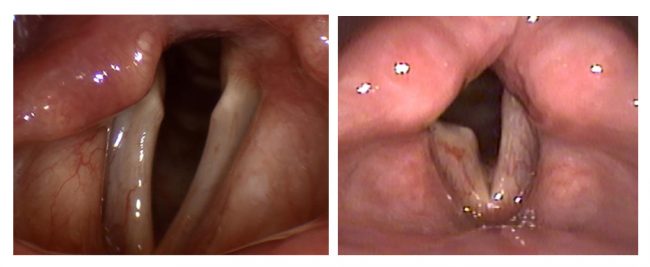

Что такое рак гортани, и кого появляется? Это один из распространенных видов рака, который можно увидеть на голосовых связках в гортани или в областях, прилегающих к голосовым связкам. Хотя это чаще встречается у мужчин, курящих и пожилых людей (40-60 лет), распространенность курения среди женщин в последние годы увеличивается из-за распространенности курения среди женщин. Алкоголь также…